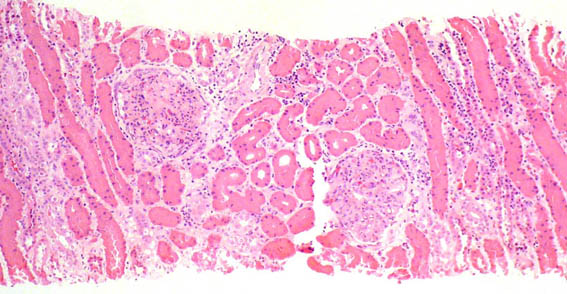

Figure 1. H&E, X100.